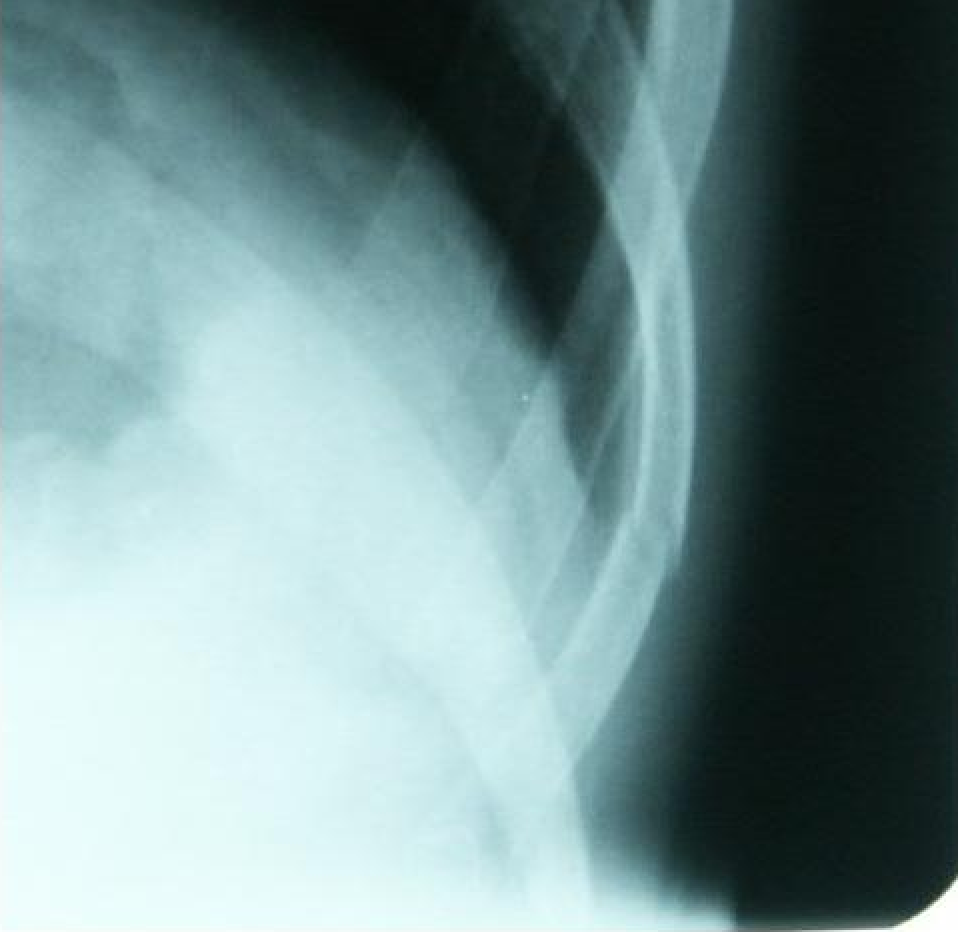

病院

会社を休んで病院へ行った。

道志でコケてから、力んだり、咳やクシャミをすると左肋骨に激痛が走るからだ。

まぁ、暫くは痛いけど、制限事項がないのが救いかね。